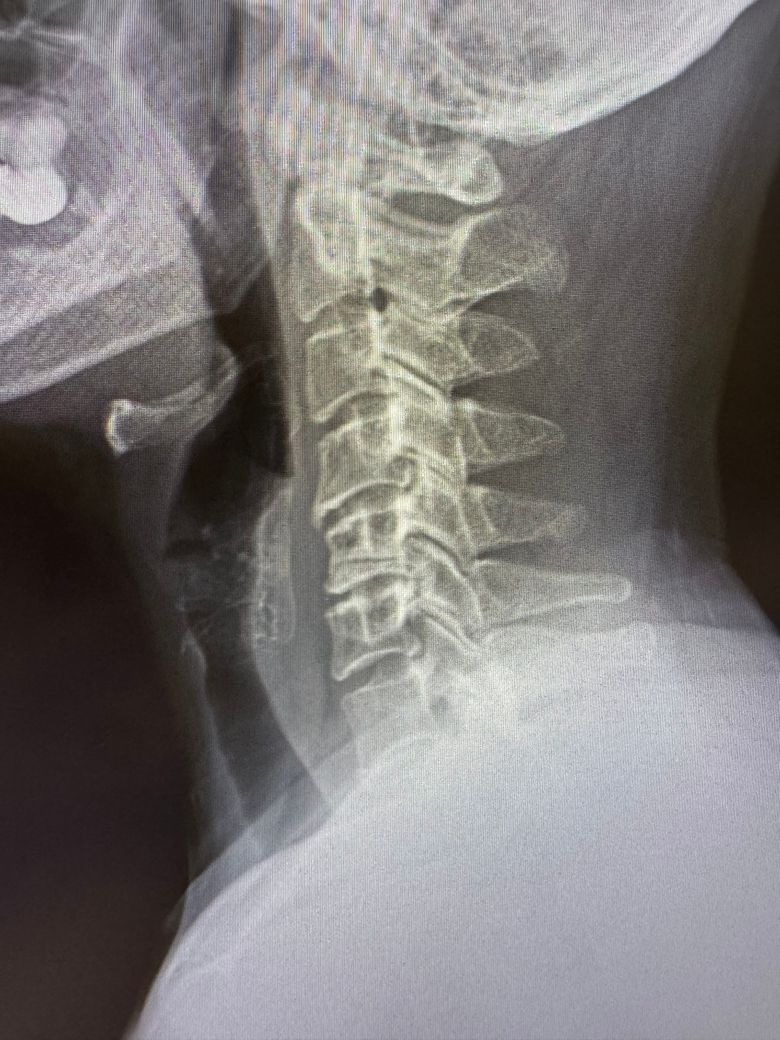

경추 골절인가요? 병원에서 모르겠다고...

5번 경추 가로로 있는게 골절인지 아닌지 모르겠다고..

골절이면 멀쩡할수가 없는데 뭔지 모르겠다고 솔직하게 말씀하시네요. 초보의사라면서 본인이... 골절인가요??

골절이 의심될 수 있는데요, 정확한 확인을 위해서 영상자료를 첨부하여 다른 병원에 방문하여 보시거나 상급병원에서 정밀검사를 받아보시는 방법을 추천드리겠습니다.

사진상으로는 정확한 상태를 확인하기는 어려우나 일단 공유해주신 사진상으로는 크게 골절이 확인 되지는 않습니다.

그렇지만 통증 및 증상이 지속되시거나 하신다면 가까운 다른 병원에 방문하시어 추가적인 검사를 통해 상태를 확인해보시는 것도 좋은 방법이 될 것으로 생각됩니다.

사진상으로 많은걸확인할수는없습니다 하지만 엑스레이상으로는 골절이나 이상이 보이지는않습니다 따라서 골절이의심되고 확인해보고싶다면 다른각도에서 엑스레이를찍어보시거나 MRI검사를받아보시길 바랍니다 감사합니다~!

5번 경추의 가로롤 있는 부분이 골절인지 여부는 엑스레이나 mri 검사로 정확히 판단해야 합니다 골절이 발생하면 통증, 부종, 이동제한 등의 증상이 나타날 수 있지만 경미한 골절은 증상이 경미할 수 도 있습니다 초보 의사의 의견이라도 추가적인 검사가 필요하다면 다른 전문의와 상담하여 확실한 진단을 받는 것이 중요합니다! 골절 여부와 상관없이 목 통증이 지속된다면 반드시 전문가의 진료를 받는 것이 좋습니다!